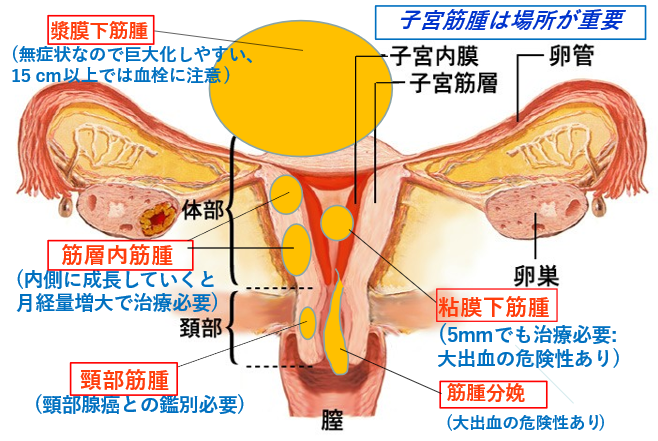

子宮筋腫ウイメンズクリニック南麻布 清水敬生港区 南麻布の婦人科。